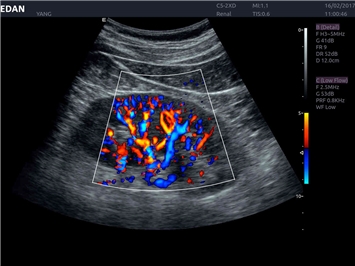

Энергетический допплер:

Да

Общая визуализация: